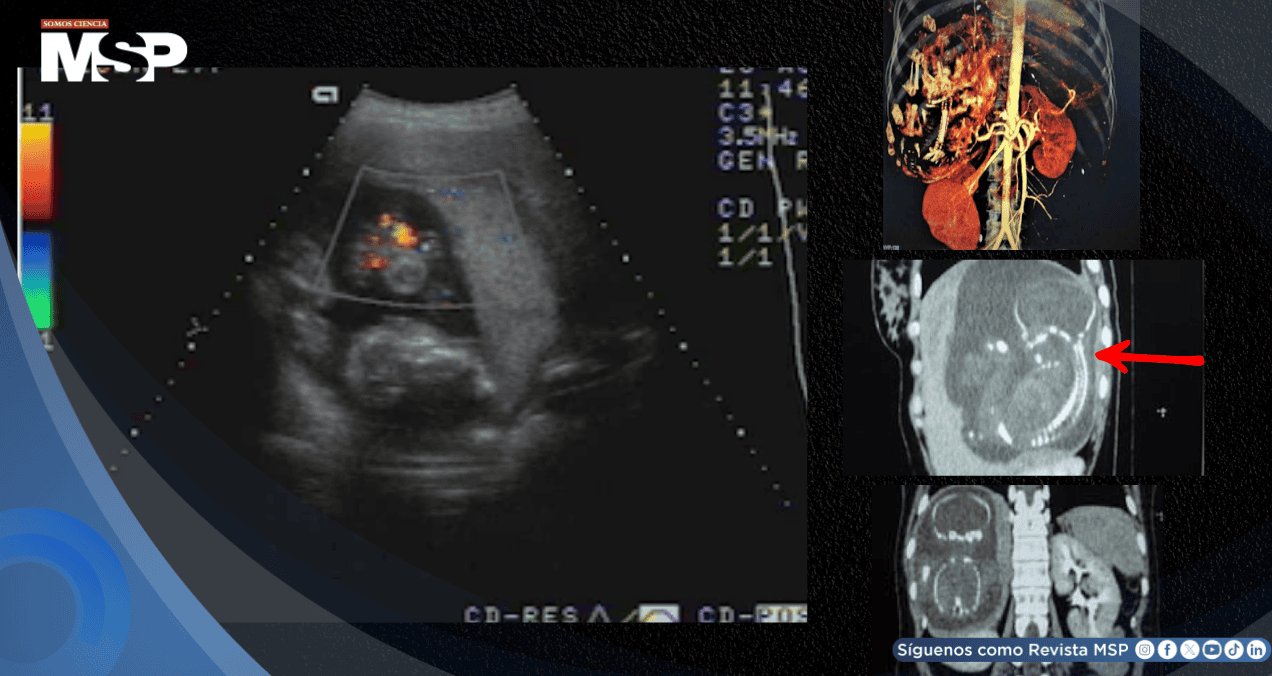

Este síntoma motivó la realización de estudios de imagen más exhaustivos en el Centro Médico MEDIC y el Hospital T? Du de Ciudad Ho Chi Minh. La ecografía abdominal reveló un feto de 23 semanas de gestación, con latidos cardíacos positivos, desarrollándose dentro del hígado de la paciente.

La confirmación definitiva llegó el 28 de agosto de 2007 mediante tomografía computarizada, que estableció sin lugar a dudas la presencia de un embarazo hepático de 23 semanas, localizado completamente dentro del parénquima del lóbulo hepático derecho.

Los estudios de angiotomografía computarizada multifocal con contraste revelaron detalles vasculares críticos: los vasos de la bolsa fetal se originaban directamente de la arteria hepática, y la placenta mostraba una adherencia significativa al tejido hepático, características que explicaban la viabilidad del embarazo pero que simultáneamente representaban un riesgo vital inminente.

Las imágenes diagnósticas permitieron caracterizar este raro embarazo abdominal. La masa fetal medía 12 x 15 x 17 centímetros, ubicándose en el abdomen, por debajo del diafragma derecho y dentro del lóbulo hepático derecho.

La placenta, con un grosor considerable de 47 milímetros, mostraba una invasión directa del hígado derecho y recibía su irrigación vascular principalmente de la arteria hepática derecha, configuración anatómica que convertía cualquier intervención en un procedimiento de altísimo riesgo por la vascularización extremadamente abundante.